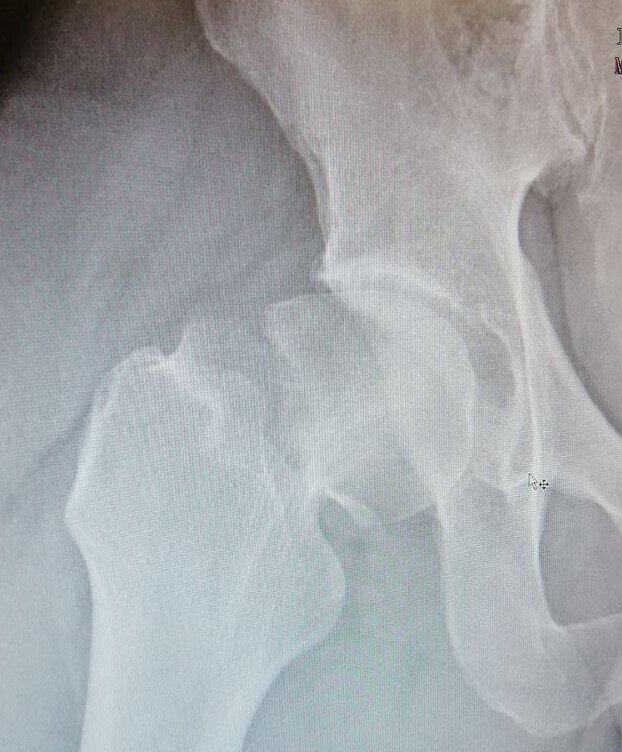

В апреле 21-го шурупы вынули, нога вернулась к своим любимым занятиям, но.... Увы, полного восстановления не случилось, ноге становилось все хуже и хуже. В конечном итоге она уже и ходить -то не могла толком. И выглядела так, грустно и печально: